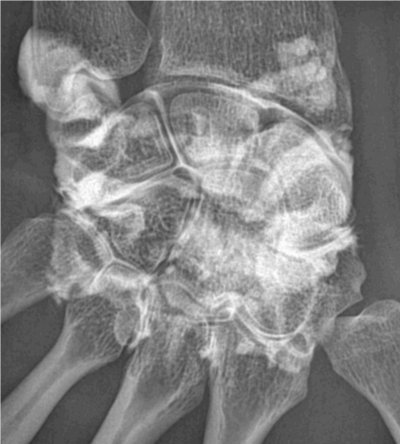

Poignet

Rupture du ligament triangulaire (flèche de droite)

Rupture des ligaments ulno-carpien et luno-pyramydal, chondropathie dégénérative (flèche du bas)